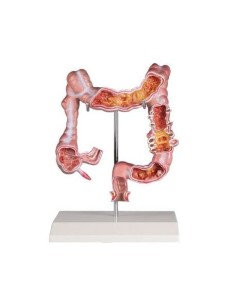

3B Modèle scientifique et anatomique : Pathologies de l'intestin K55